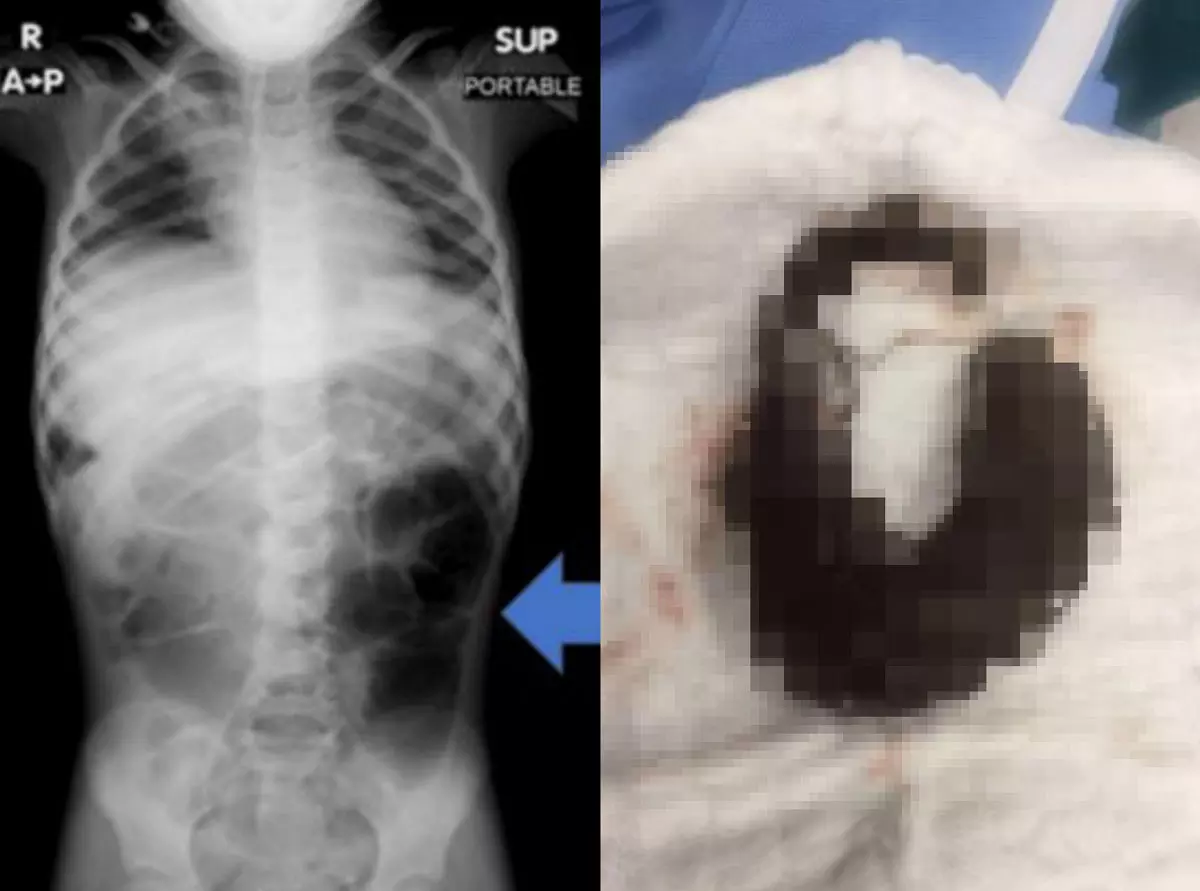

의료진은 복통 영상 검사를 시행했고, 위장 내 큰 이물질이 발견됐다. 정체는 바로 머리카락 덩어리였다. 머리카락 덩어리는 위에서 소장까지 길게 이어진 모습이었다.

여아는 절개술을 통해 머리카락 덩어리를 제거했다. 수술 후에는 소아 정신과 치료를 통해 재발을 예방했다. 의료진은 “반복적인 복통, 구토, 식욕 부진이 오래 지속될 때 의심해야 한다”며 “영상 검사를 통해 조기에 발견하고 빠른 치료가 시행돼야 한다”고 말했다.